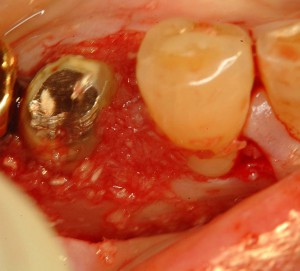

根面清掃後

根面清掃後